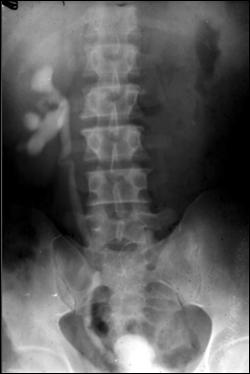

Diagnosticul diferential cu tuberculoza urogenitala

Vezica urinara are contururi greu delimitabile pe cistografie si pacientul are ureterohidronefroza bilaterala.

Figura 57. Vezica urinara mica |

Vezica urinara mica, scleroasa, cu rinichi drept unic chirurgical, uretero-hidronefroza gr I

Figura 59. Vezica urinara "crispata", cu ureterohidronefroza bilaterala. |